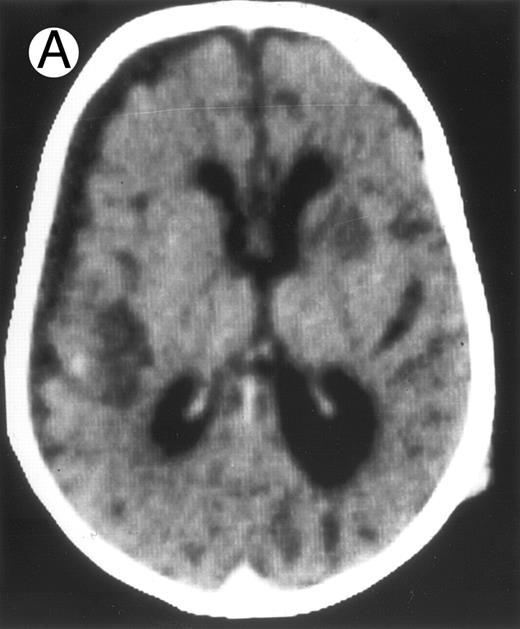

Three different aspects of brain imaging in HLH patients. (A) CT scan of a 3-month-old baby showing a large subdural effusion, several necrotic areas and hypodensities of the white matter. (B) Brain magnetic resonance of a 14-month-old boy showing large confluent areas of hypersignal in T2-weighted images. (C) Large symmetrical necrotic areas of cerebellar white matter in a 41/2-year-old girl (MRI).

Among the nine children with initial neurological symptoms, seizures were the most frequent initial symptom in the youngest patients, whereas ataxia was found in the two oldest patients (46 and 58 months old, respectively) (Table 1). All nine patients had the same CSF abnormalities as patients with meningitis only. Eight of these nine patients had a neuroradiological study performed at the time of their first neurological symptoms (Table 1). The two most frequent lesions were focal necrosis with parenchymal volume loss and atrophy (Fig 2A and C) and white matter abnormalities (Fig 2B). Several small focal lesions with hypersignal at MR imaging that enhanced after administration of gadopentate dimeglumine (or contrast on CT scan) were also observed in two cases.